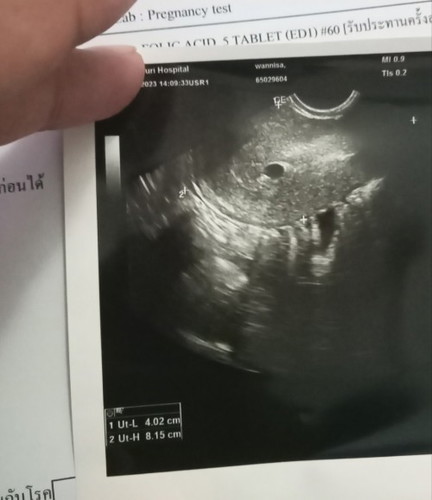

หมอบอกให้โอกาสน้องอีก 2 อาทิต เพราะถุงตั้งครรภ์แค่ 5 วีค มีเลือดออก โอกาสแท้ง 50% โอกาสรอด 50% ถ้าซาวรอบต่อไปแล้วเจอถุงไข่แดงน้อง#ขอบคุณล่วงหน้านะคะ #ขอคำแนะนำหน่อยค่ะ #ขอบคุณสำหรับคำตอบค่ะ

แม่บ้านนี้ก็มีเลือดออกตอน 5 วีค หมอซาวเจอถุงตั้งครรภ์ แต่ไม่เจอตัวน้อง รอ 9 วีน ไปซาวอีกรอบ ก็เจอค่ะ คุณแม่ใจเย็นๆน่า น้องอาจจะเล็กอยู่